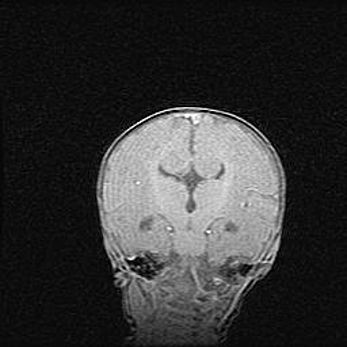

Церебральная ишемия II.

Возраст: 5 дней

Вес: 3400 г

Пол: женский

Окружность головы: 35 см

Срок гестации: 39 недель

Церебральная ишемия – это заболевание, характеризующееся недостаточностью (гипоксией) либо полным прекращением (аноксией) снабжения мозга кислородом по причине закупорки одного или нескольких сосудов. Это приводит к  что метаболическим расстройствам различной степени тяжести в тканях головного мозга, развитию коагуляционных некрозов и гибели нейронов.